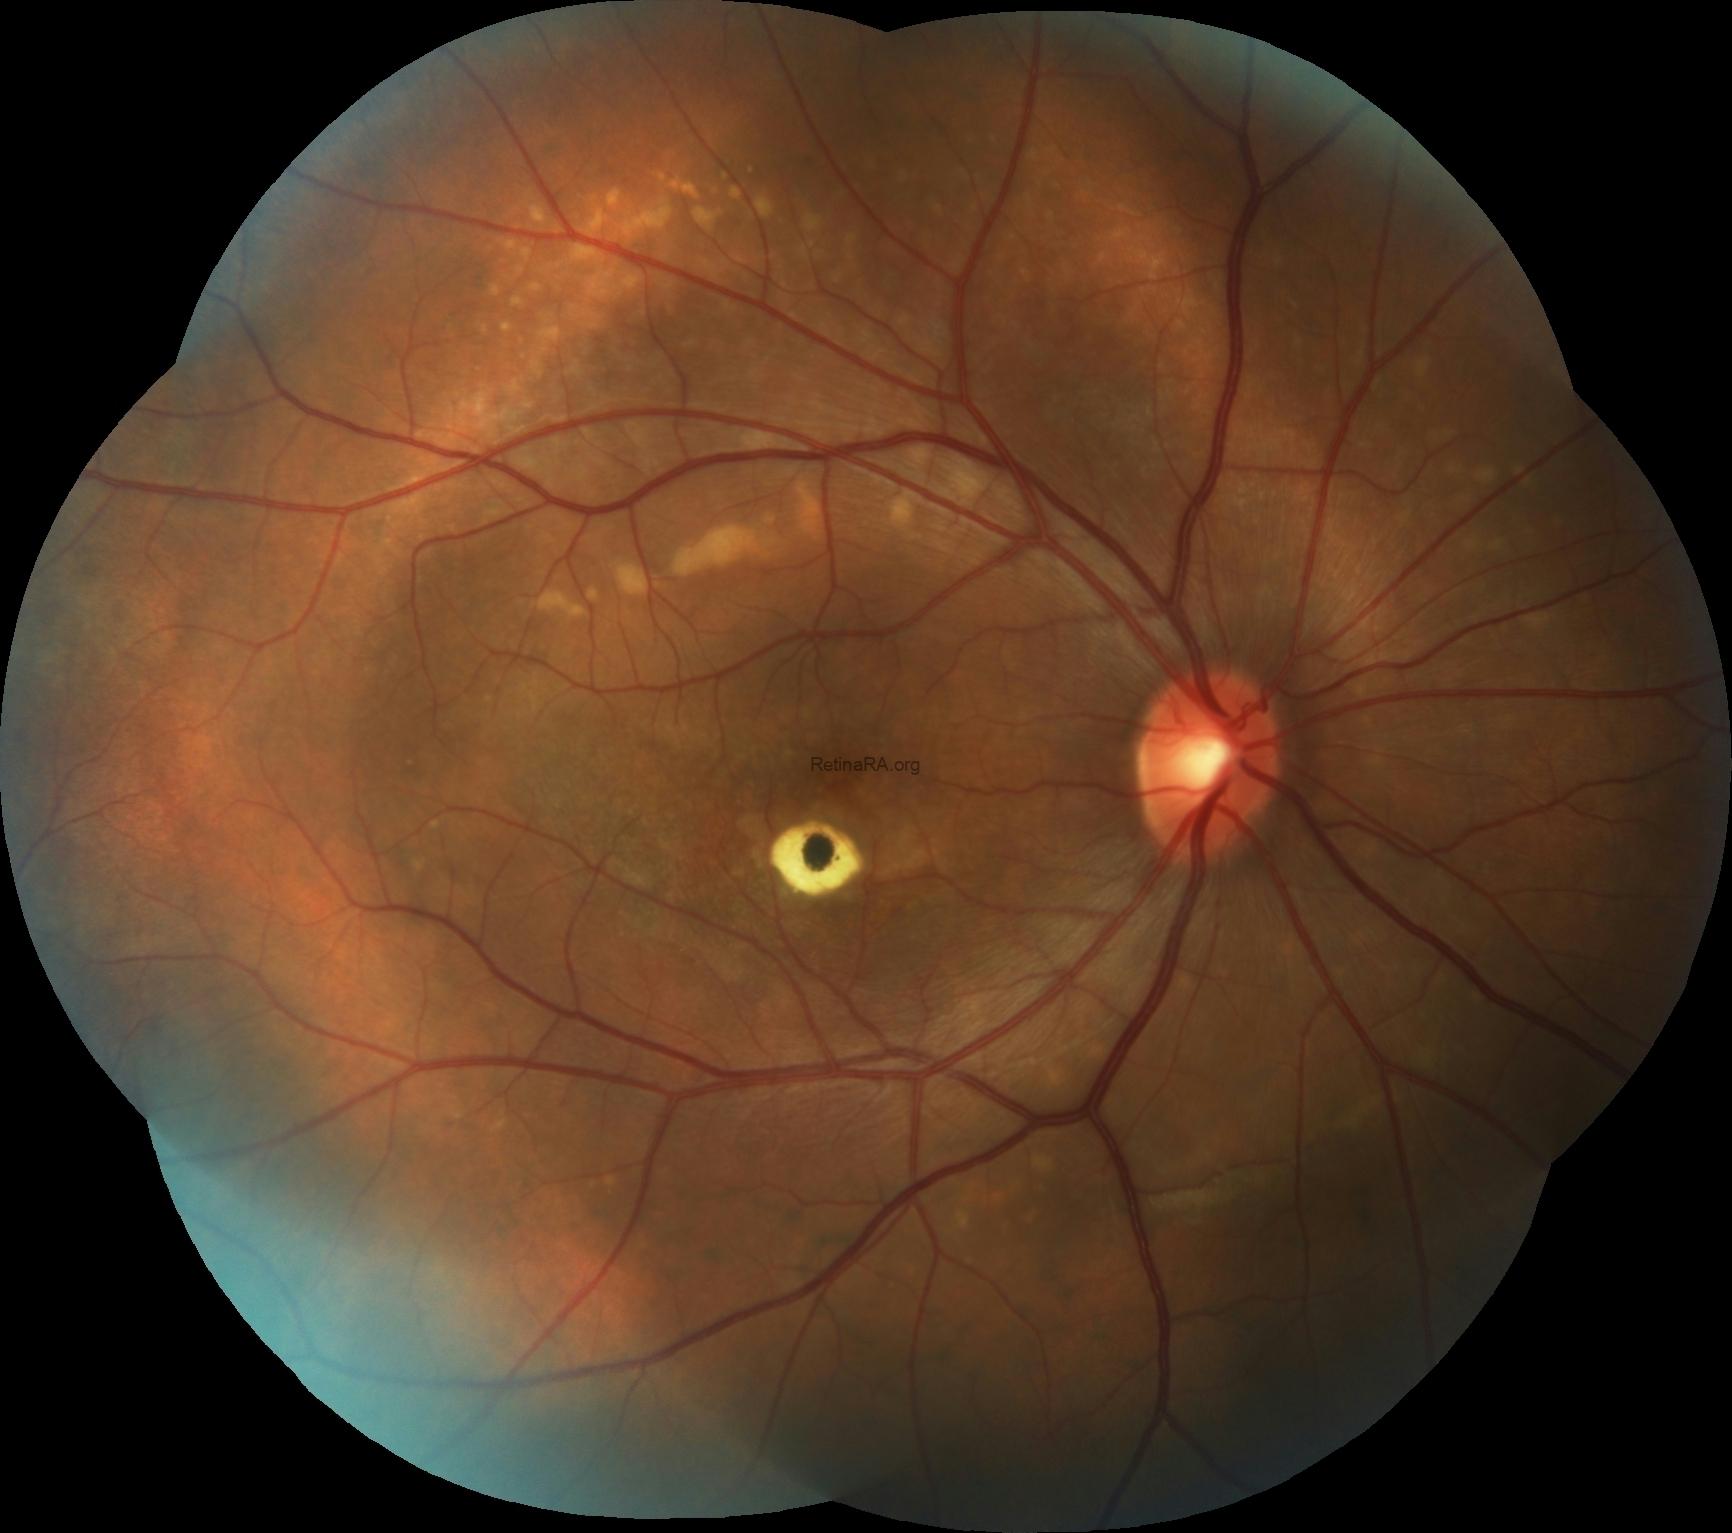

Dilated fundus examination demonstrated centrally hyperpigmented macular scar in the right eye and focal hypopigmented RPE atrophy at the inferior of fovea in the left eye in addition to bilateral multifocal subretinal white-yellow deposits in the macula and posterior pole of both eyes.

Fundus autofluorescence imaging exhibited that the central hyperpigmentation was hypo-autofluorescent while its surroundings were hyper- autofluorescent in the right foveal region with mixed or decreased autofluorescence at the inferior of fovea in the left eye as well as the deposits were brightly autofluorescent in both eyes.

Fluorescein angiography imaging showed that the central hyperpigmentation was hypofluorescent due to blockage while its surroundings were window-defect hyperfluorescent in the right foveal region, with the window-defect hyperfluorescent at inferior of fovea in the left eye besides the staining of the subretinal deposits in both eyes.